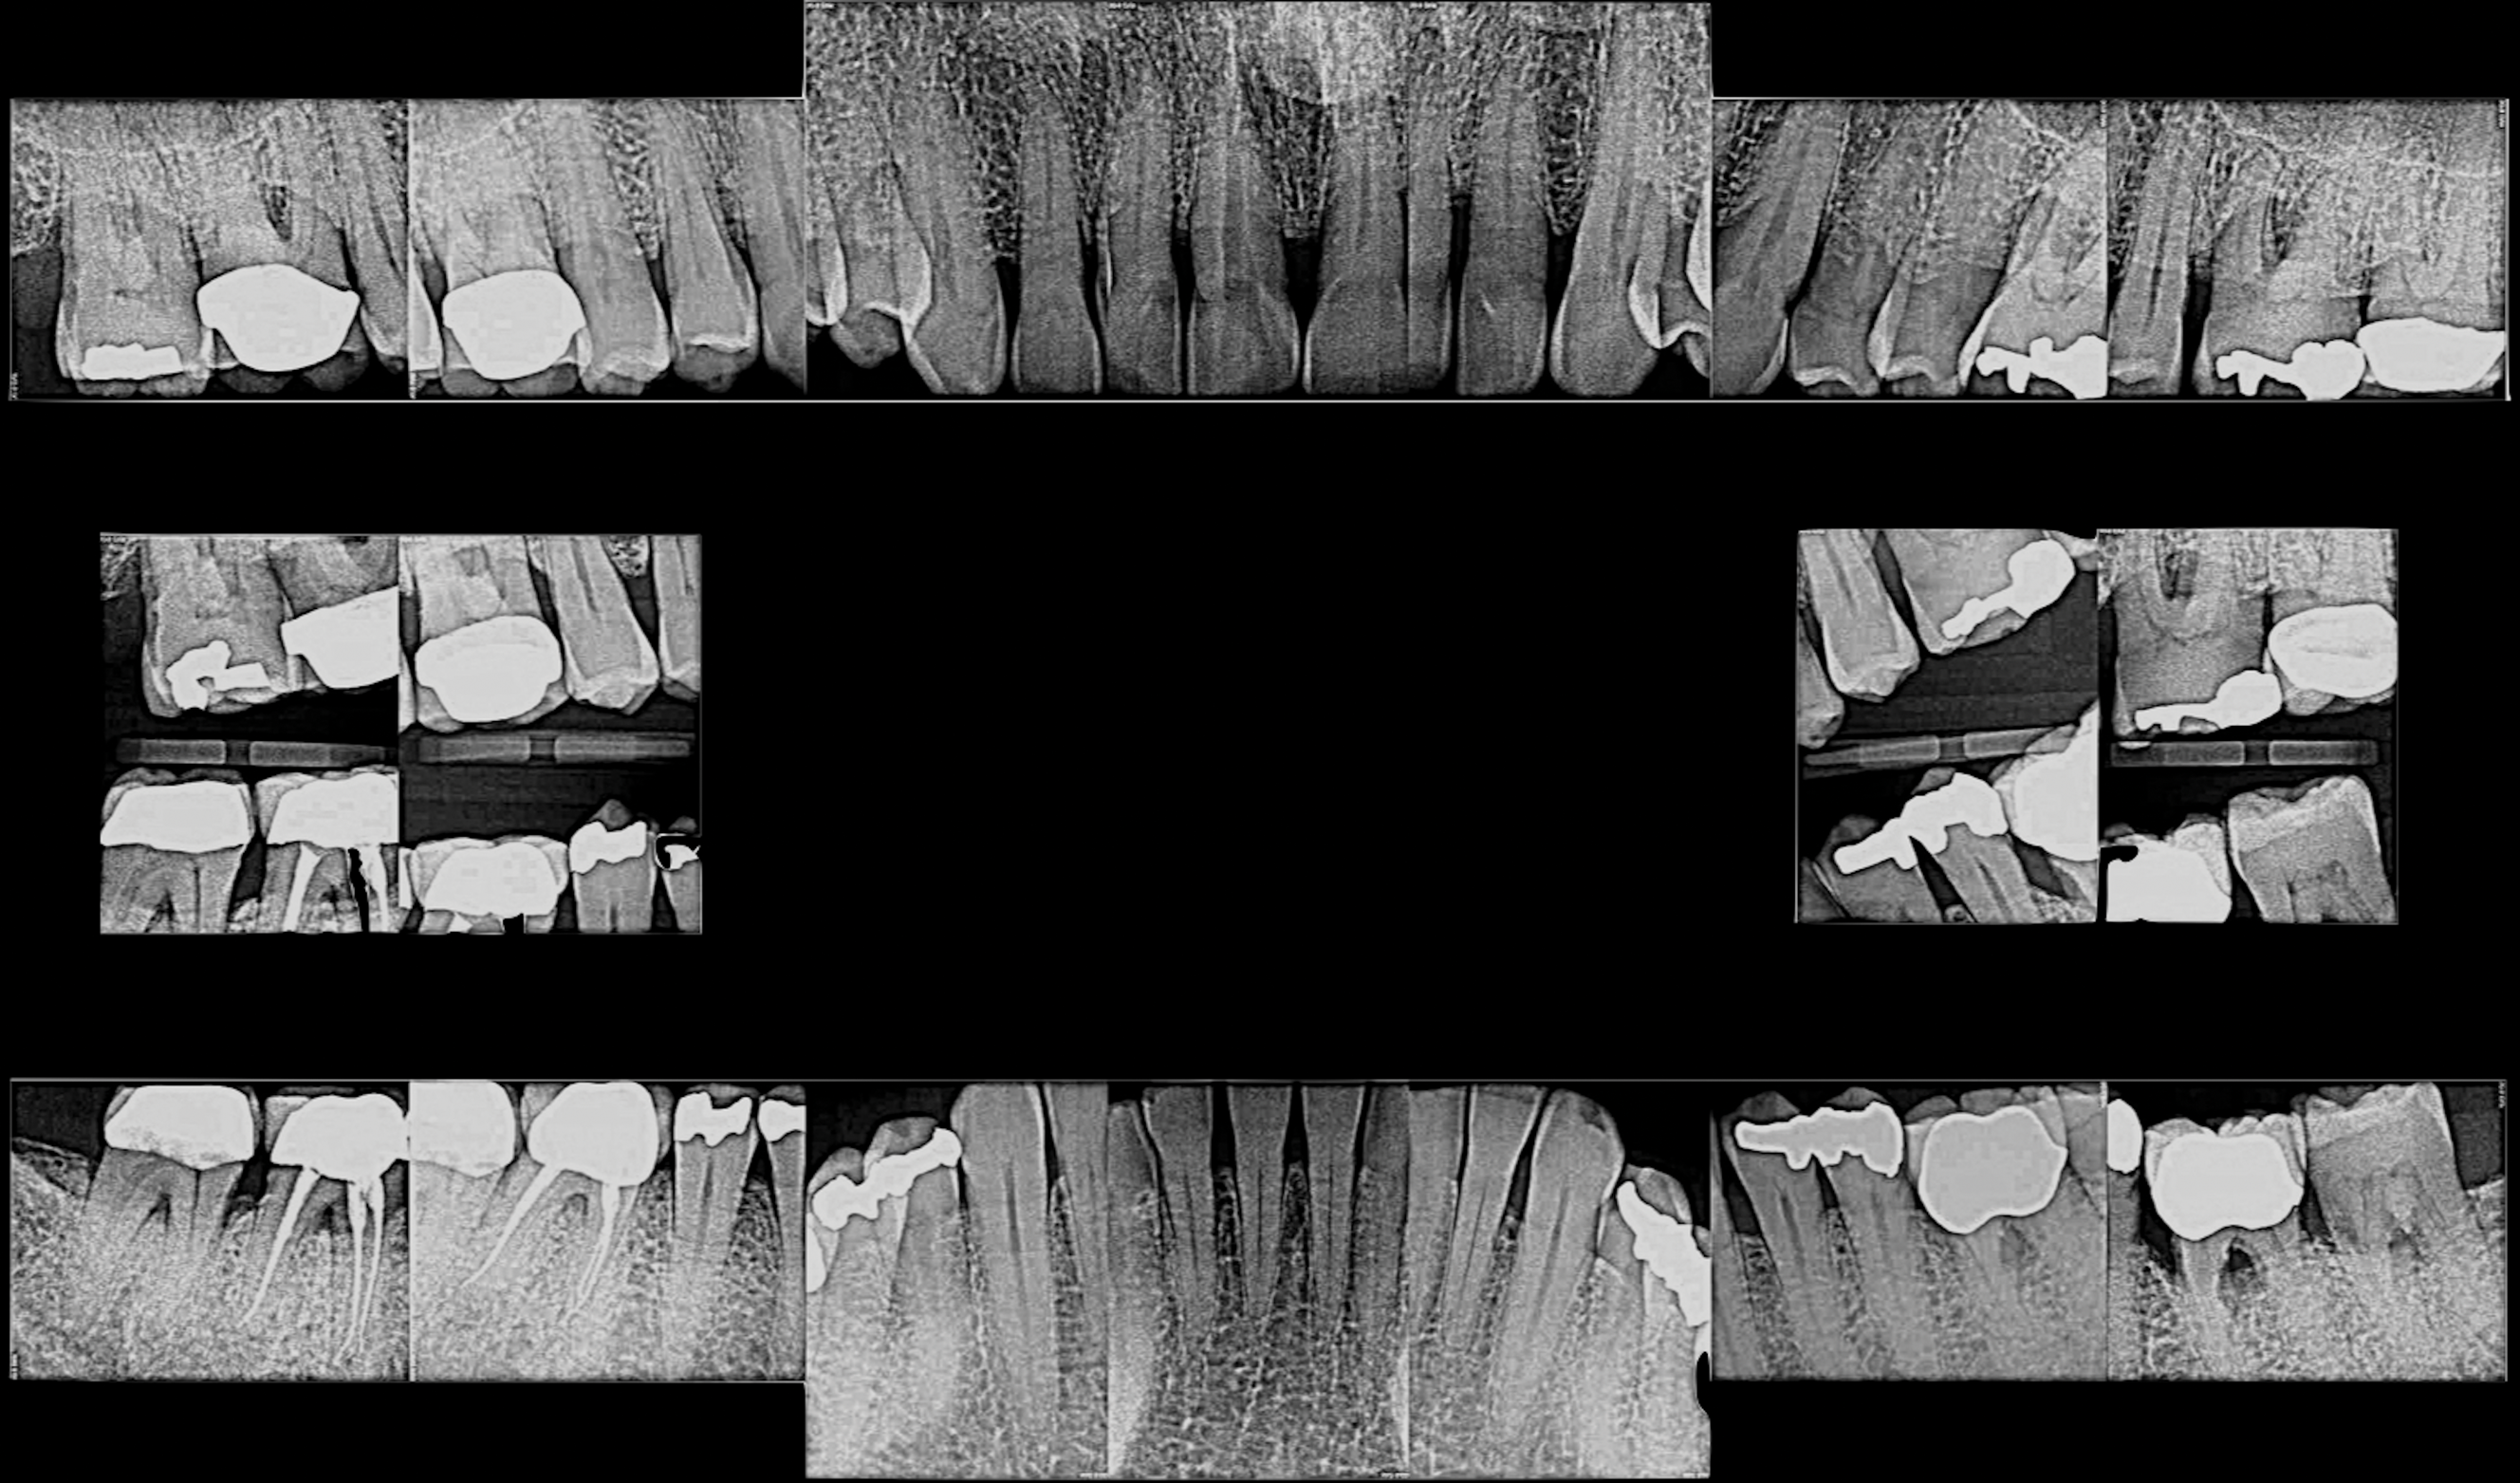

Fig 7. Pretreatment periapical radiographs.

Figure 7

Periodontal examination revealed generalized BOP and PDs up to 9 mm in the maxillary and mandibular molars with multiple furcations in each molar (Figure 2 through Figure 7). He presented with class I mobility in many posterior teeth and class II mobility in teeth Nos. 3 and 9 (maxillary right first molar and maxillary left central incisor, respectively). The periodontist decided to score tooth No. 3 for the PRS, as this was the most periodontally involved molar that was planned to be treated and maintained (Figure 2 and Figure 8). This tooth (maxillary right first molar = score 1) presented with probing depths of 7 mm (score 1); three total furcation invasions (score 3) (mesial [degree II furcation], buccal [degree I furcation], and distal [degree II furcation]); and a class II mobility (score 2). The total PRS for tooth No. 3 was 8, representing a "guarded" prognosis. Based on this score, the likelihood of not losing any teeth to periodontal disease for 15 years was 81%, and for 30 years the likelihood was just 56% (Figure 9).7

The periodontist felt that teeth Nos. 17 and 18 (mandibular left third and second molars, respectively) had a questionable prognosis due to severe periodontal attachment loss, class III furcations, and probable furcation caries as detected on radiographs. These two teeth were treated the same as the others with the patient being advised that they may need either retreatment or extraction in the future with dental implants possibly being recommended.